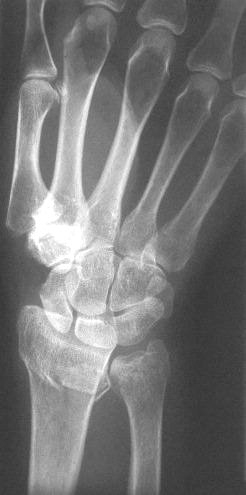

Clinical Example: Distraction plate fixation distal radius fracture

distal radius fracture